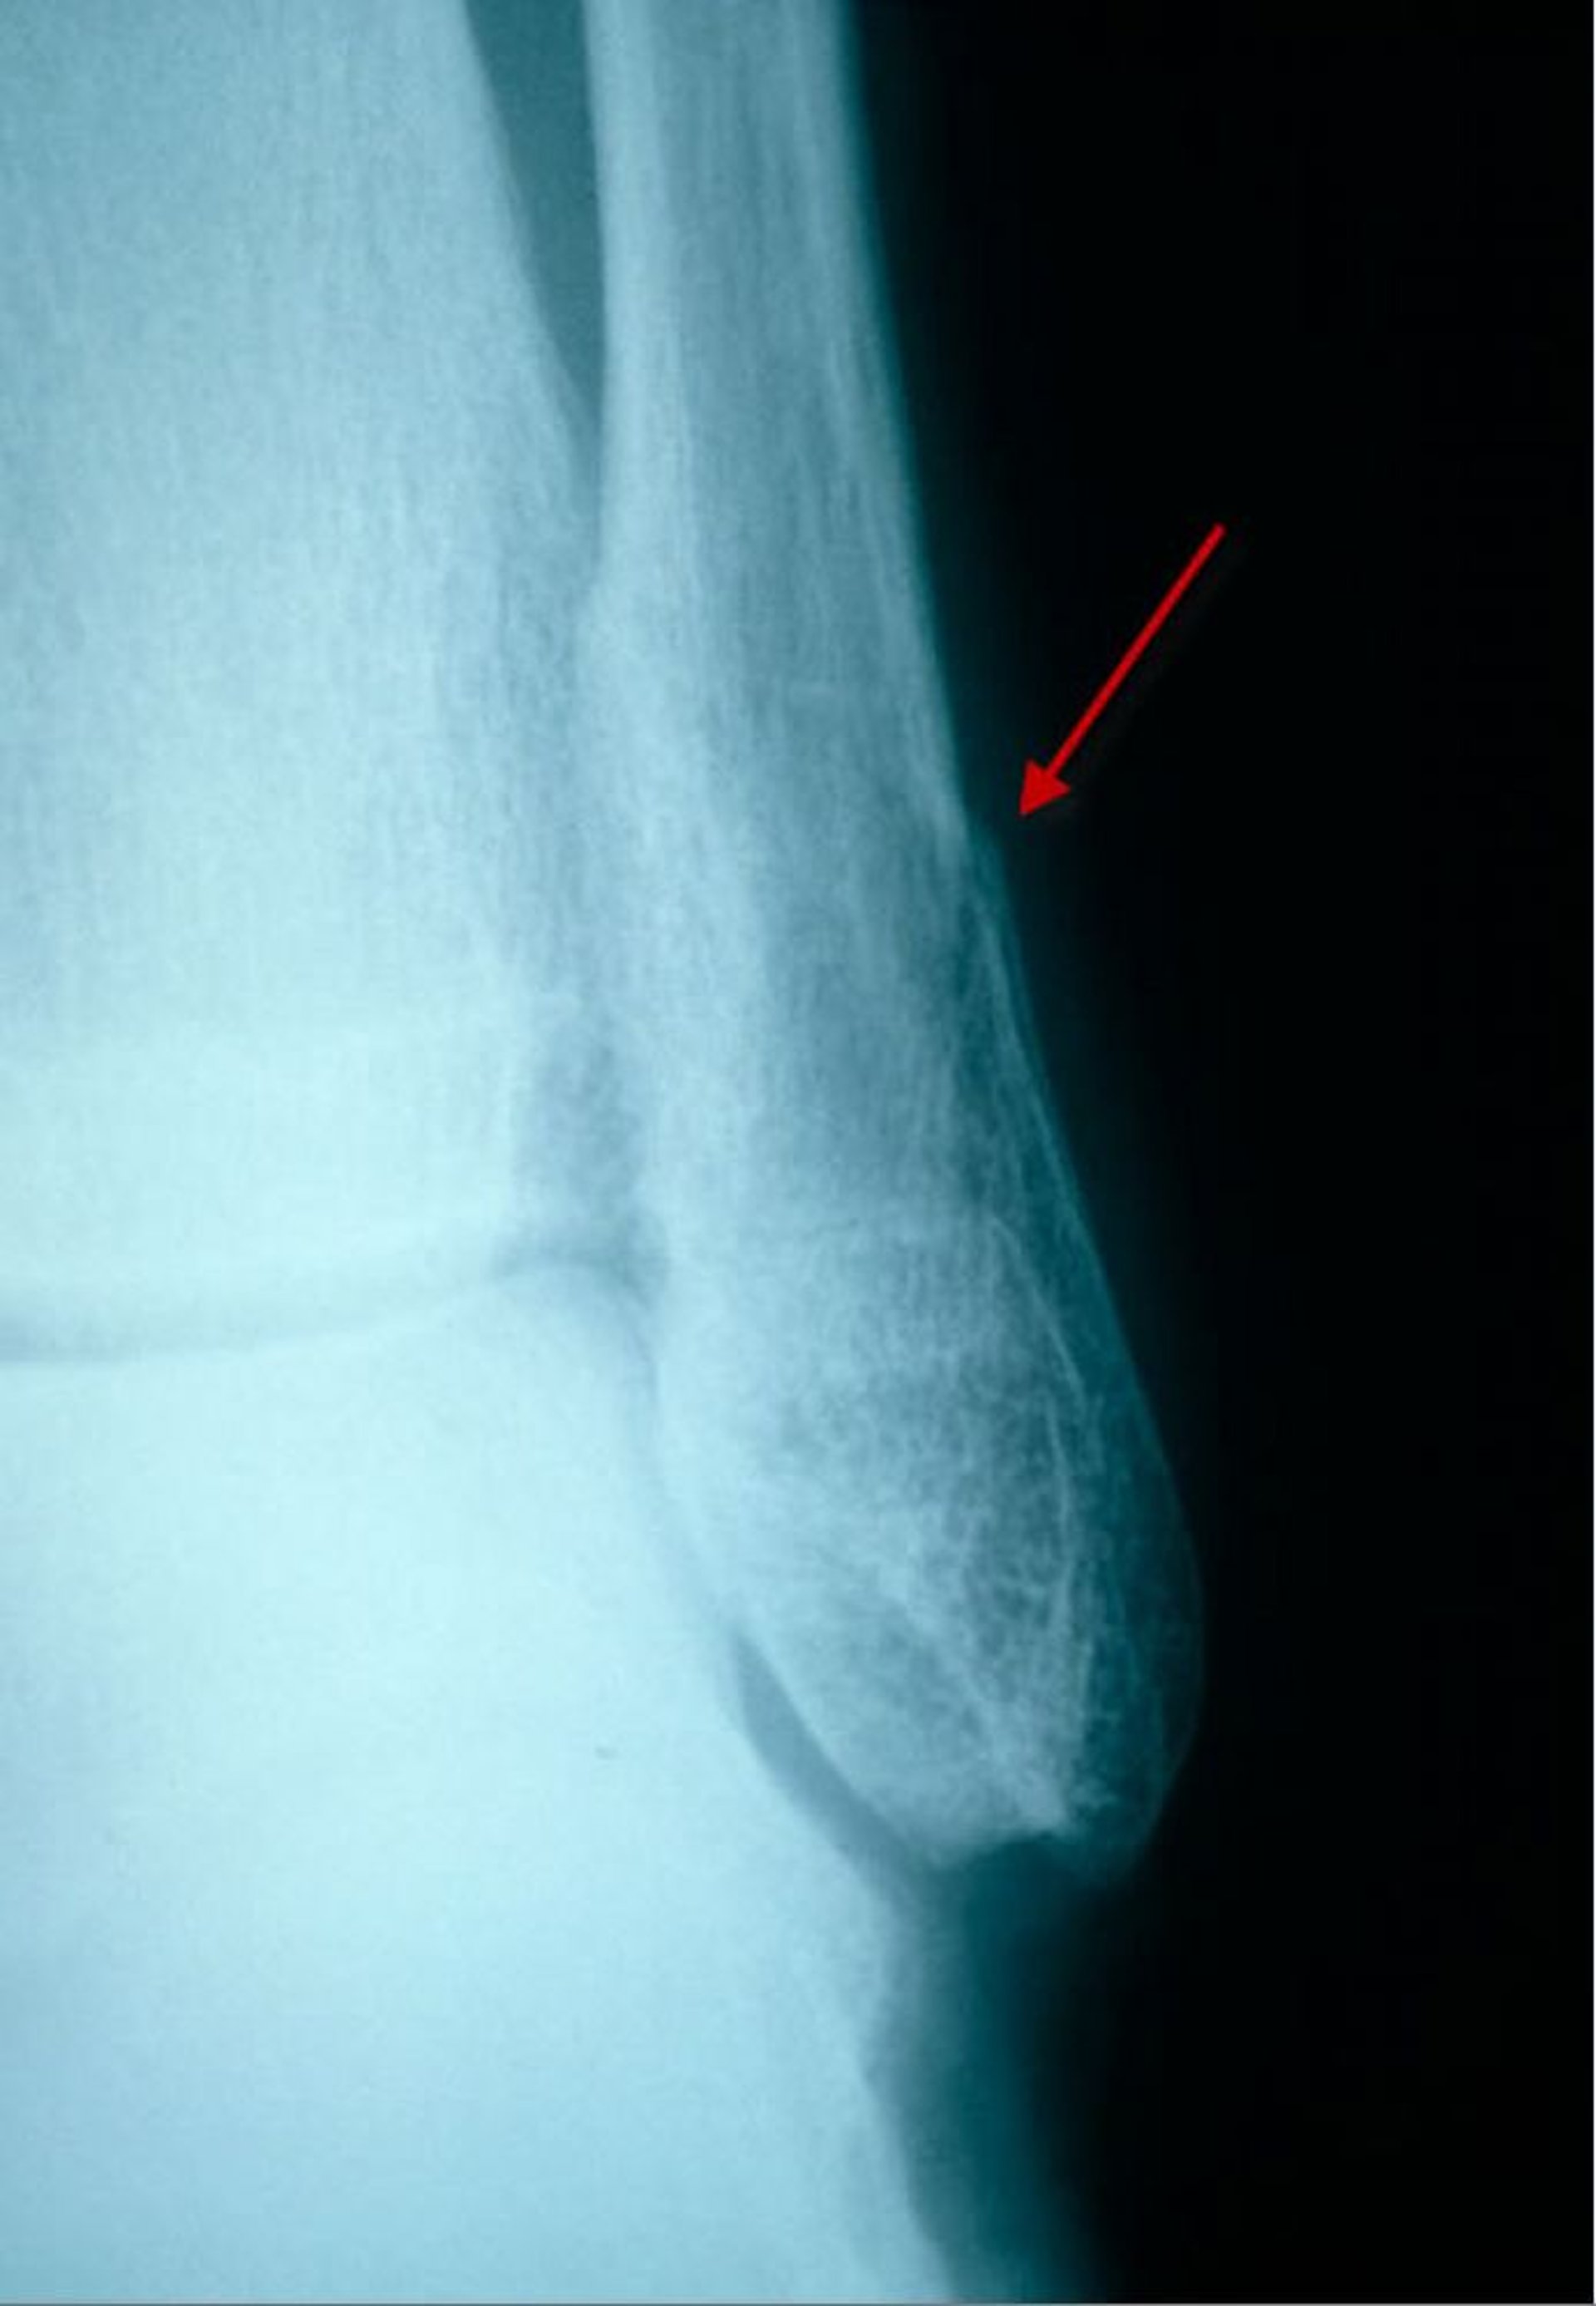

Subtile distale Fibulafraktur (Laterale Ansicht)

In dieser lateralen Ansicht ist eine Fraktur der distalen Fibula als kleine Aufhellung und Diskontinuität (Abstoßung) der Kortikalis sichtbar.